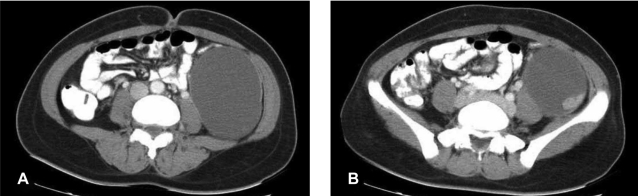

A 32-year-old married woman was referred to the surgical unit because of a self-palpable mass in her left lower abdomen for over 1 month and the abdominal pain for the recent several days. Physical examination revealed a slightly tender, ill-defined mass about 10 cm in size over the left lower abdomen. The laboratory tests, including the complete blood count, the chemistry profile, urinalysis and chest X-ray, were all within normal limits. Abdominopelvic computed tomography scanning revealed a huge unilocular cystic mass with an enhancing solid portion, and this was probably located in the retroperitoneal space (Figure 1A, 1B). There was no evidence of extracystic extensi on or distant metastasis.

Figure 1

(A) Abdominopelvic computed tomography shows a large unilocular cystic mass in the left retroperitoneal space. (B) There is an enhancing solid portion in the posterolateral aspect of the inner surface of the cyst.